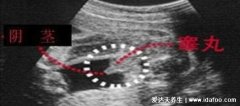

2、3条线是女孩

如果是这样的,3条线的标志,正好对应女孩的小阴唇,是比较明显的特征。